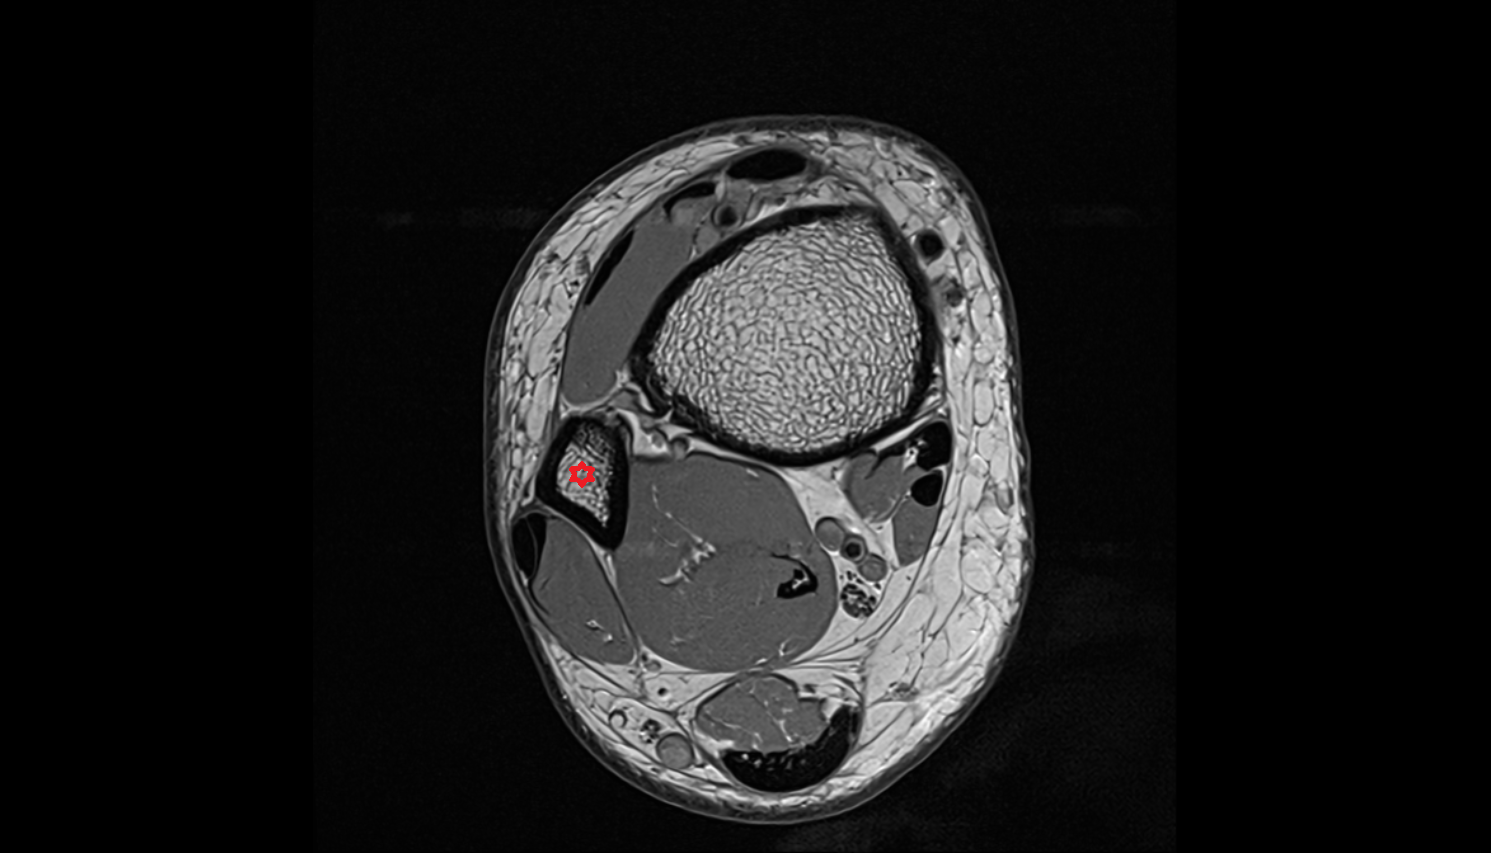

- Body of tibia

- Tibia

- Fibula

- Tibialis posterior muscle

- Flexor digitorum longus muscle

- Flexor hallucis longus muscle